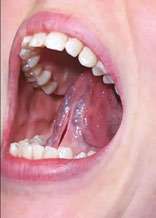

Intraoral examination revealed narrow, flattened dental arches and posterior overjet (Figure 2A-D). Teeth crowding was present in both jaws, along with a midline discrepancy (Figure 2A-D). The tongue appeared wide, with scalloped edges (see the right image in Figure 5A). A thick, very tight, restrictive lingual frenal attachment was noted (Figure 2D and 2E).

After a mixture of Lidocaine 2% with 1:100,000 epinephrine was administered by local infiltration, the LightScalpel laser frenuloplasty was performed to release both the maxillary labial and lingual restrictions. LightScalpel® CO2 laser (LightScalpel, LLC, Bothell, WA) with 0.25 mm focal spot size laser handpiece was utilized, delivering 2 watts repeat, non-SuperPulse laser beam gated at 50% duty cycle at 20 Hz (average power to the tissue was 1 watt). For efficient incision, in order to create tension and ensure that the larger vasculature is pushed away from the surgical site, the patient was asked to put her tongue in the “suction-cup” position (Figure 3A). (OMT prior to a functional frenum release is necessary in order to tone the lingual muscles and ensure the patient’s ability to create and maintain tongue suction.) The dentist applied gentle traction with her fingers while performing the release (Figure 3B). When performed with scissors, this technique requires the use of a hemostat to clamp smaller blood vessels prior to sharp dissection. With the CO2 laser no hemostat is typically necessary, because smaller vasculature (under 0.5 mm) is efficiently coagulated by the 10,600 nm laser wavelength.

The laser nozzle was held 1-2 mm away from the target tissue (Figure 3B) and moved in a steady hand speed for controlled depth of incision motion. The myofunctional therapist was present throughout the entire procedure. In the course of the procedure, the dentist stopped several times, while the therapist assessed the remaining tension and the tongue mobility. First, after the dentist removed the most apparent, superficial fascial restriction, the myofunctional therapist measured the basic range of motion (ROM), palpated the tongue, using gentle experienced touch and trying to locate the presence of tightness or restriction. The patient was asked to lift, extend the tongue, and put it in the “suction-cup” position. The patient was already able to protrude and elevate her tongue better, but there was still tension and the dentist proceeded with a deeper release. At this point, no cutting was done; instead, blunt dissection was used to divide deep fascia – this technique helps the natural release, almost “melting”, of fascia. After that, the patient reported the sensation of the front neck tension alleviation. By the end of the procedure, the myofunctional therapist felt a release of the tension in the mid-portion of the tongue, where a big knot had been detected during preoperative examination. Finally, the last bit of tension detected by the myofunctional therapist was addressed by extending the incision vertically, upward, with the laser (Figure 3E).

The dentist pointed out that if she decided to not suture the surgical site, she would have ablated mucosa laterally (and created more of a diamond shape, as she does in infants and toddlers). For this patient, however, the frenum release was more linear (vertical) (Figures 3D and 3F) and sutures have been placed to facilitate healing without the need to worry about postoperative wound management to prevent return of ankyloglossia and begin OMT 72 hours postoperatively (Figure 3H).